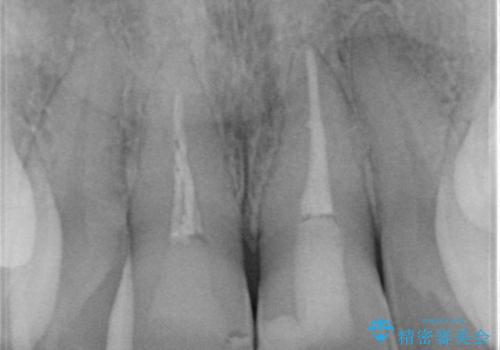

根管治療についてご説明をし、右上の1本だけ再根管治療を行うこととなりました。

- 右上1/再根管治療66,000円+ファイバーコア22,000円+仮歯11,000円+ジルコニアクラウン(スタンダード):121,000円 左上1/仮歯11,000円+ジルコニアクラウン(スタンダード)121,000円 合計352,000円(税込)費用は治療当時の料金となります